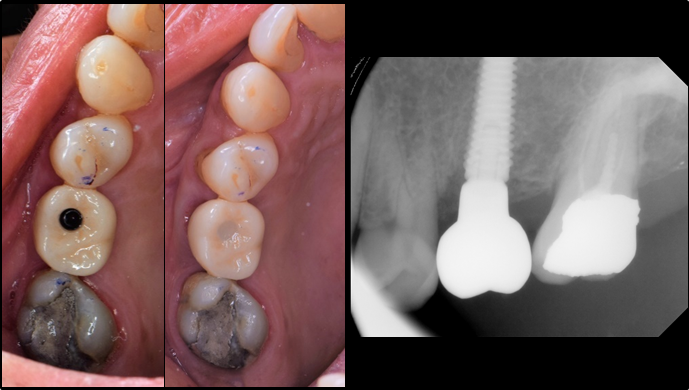

Clinical case: Immediate implant placement using R2GATE Guide & custom healing abutment

- Courtesy of Dr. Sam Omar, Egypt -

Keywords

Dr. Sam Omar, Digital Guided Surgery, Digital ONE-DAY Implant, Maxillary Posterior, #16, Guided surgery, Loading, Flapless, AnyRidge, R2GATE, MEGA ISQ, R2GATE Full surgical kit

“Prefabricated provisional restorations can serve as custom healing abutments in case of insufficient initial stability for one-day implants. ”